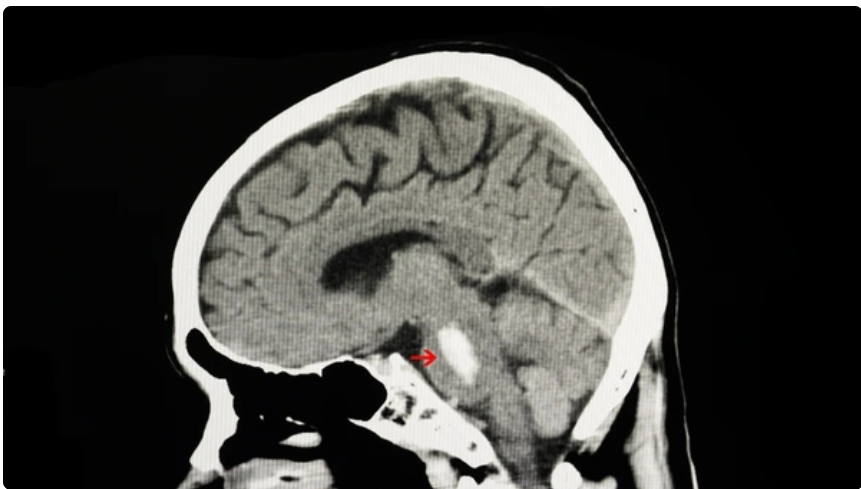

1.뇌간의 뇌교에서 발생하는 출혈로, 전체 뇌내출혈의 약 10%를 차지하지만 가장 치명적인 예후를 보이는 질환 중 하나임.

5.뇌교는 공간이 매우 제한적이며, 주위가 중요 신경핵과 상행, 하행 신경로로 밀집됨.

출혈 발생시 주변 신경조직을 압박 + 파괴하여, 소량 출혈이라도 임상적으로 치명적임.